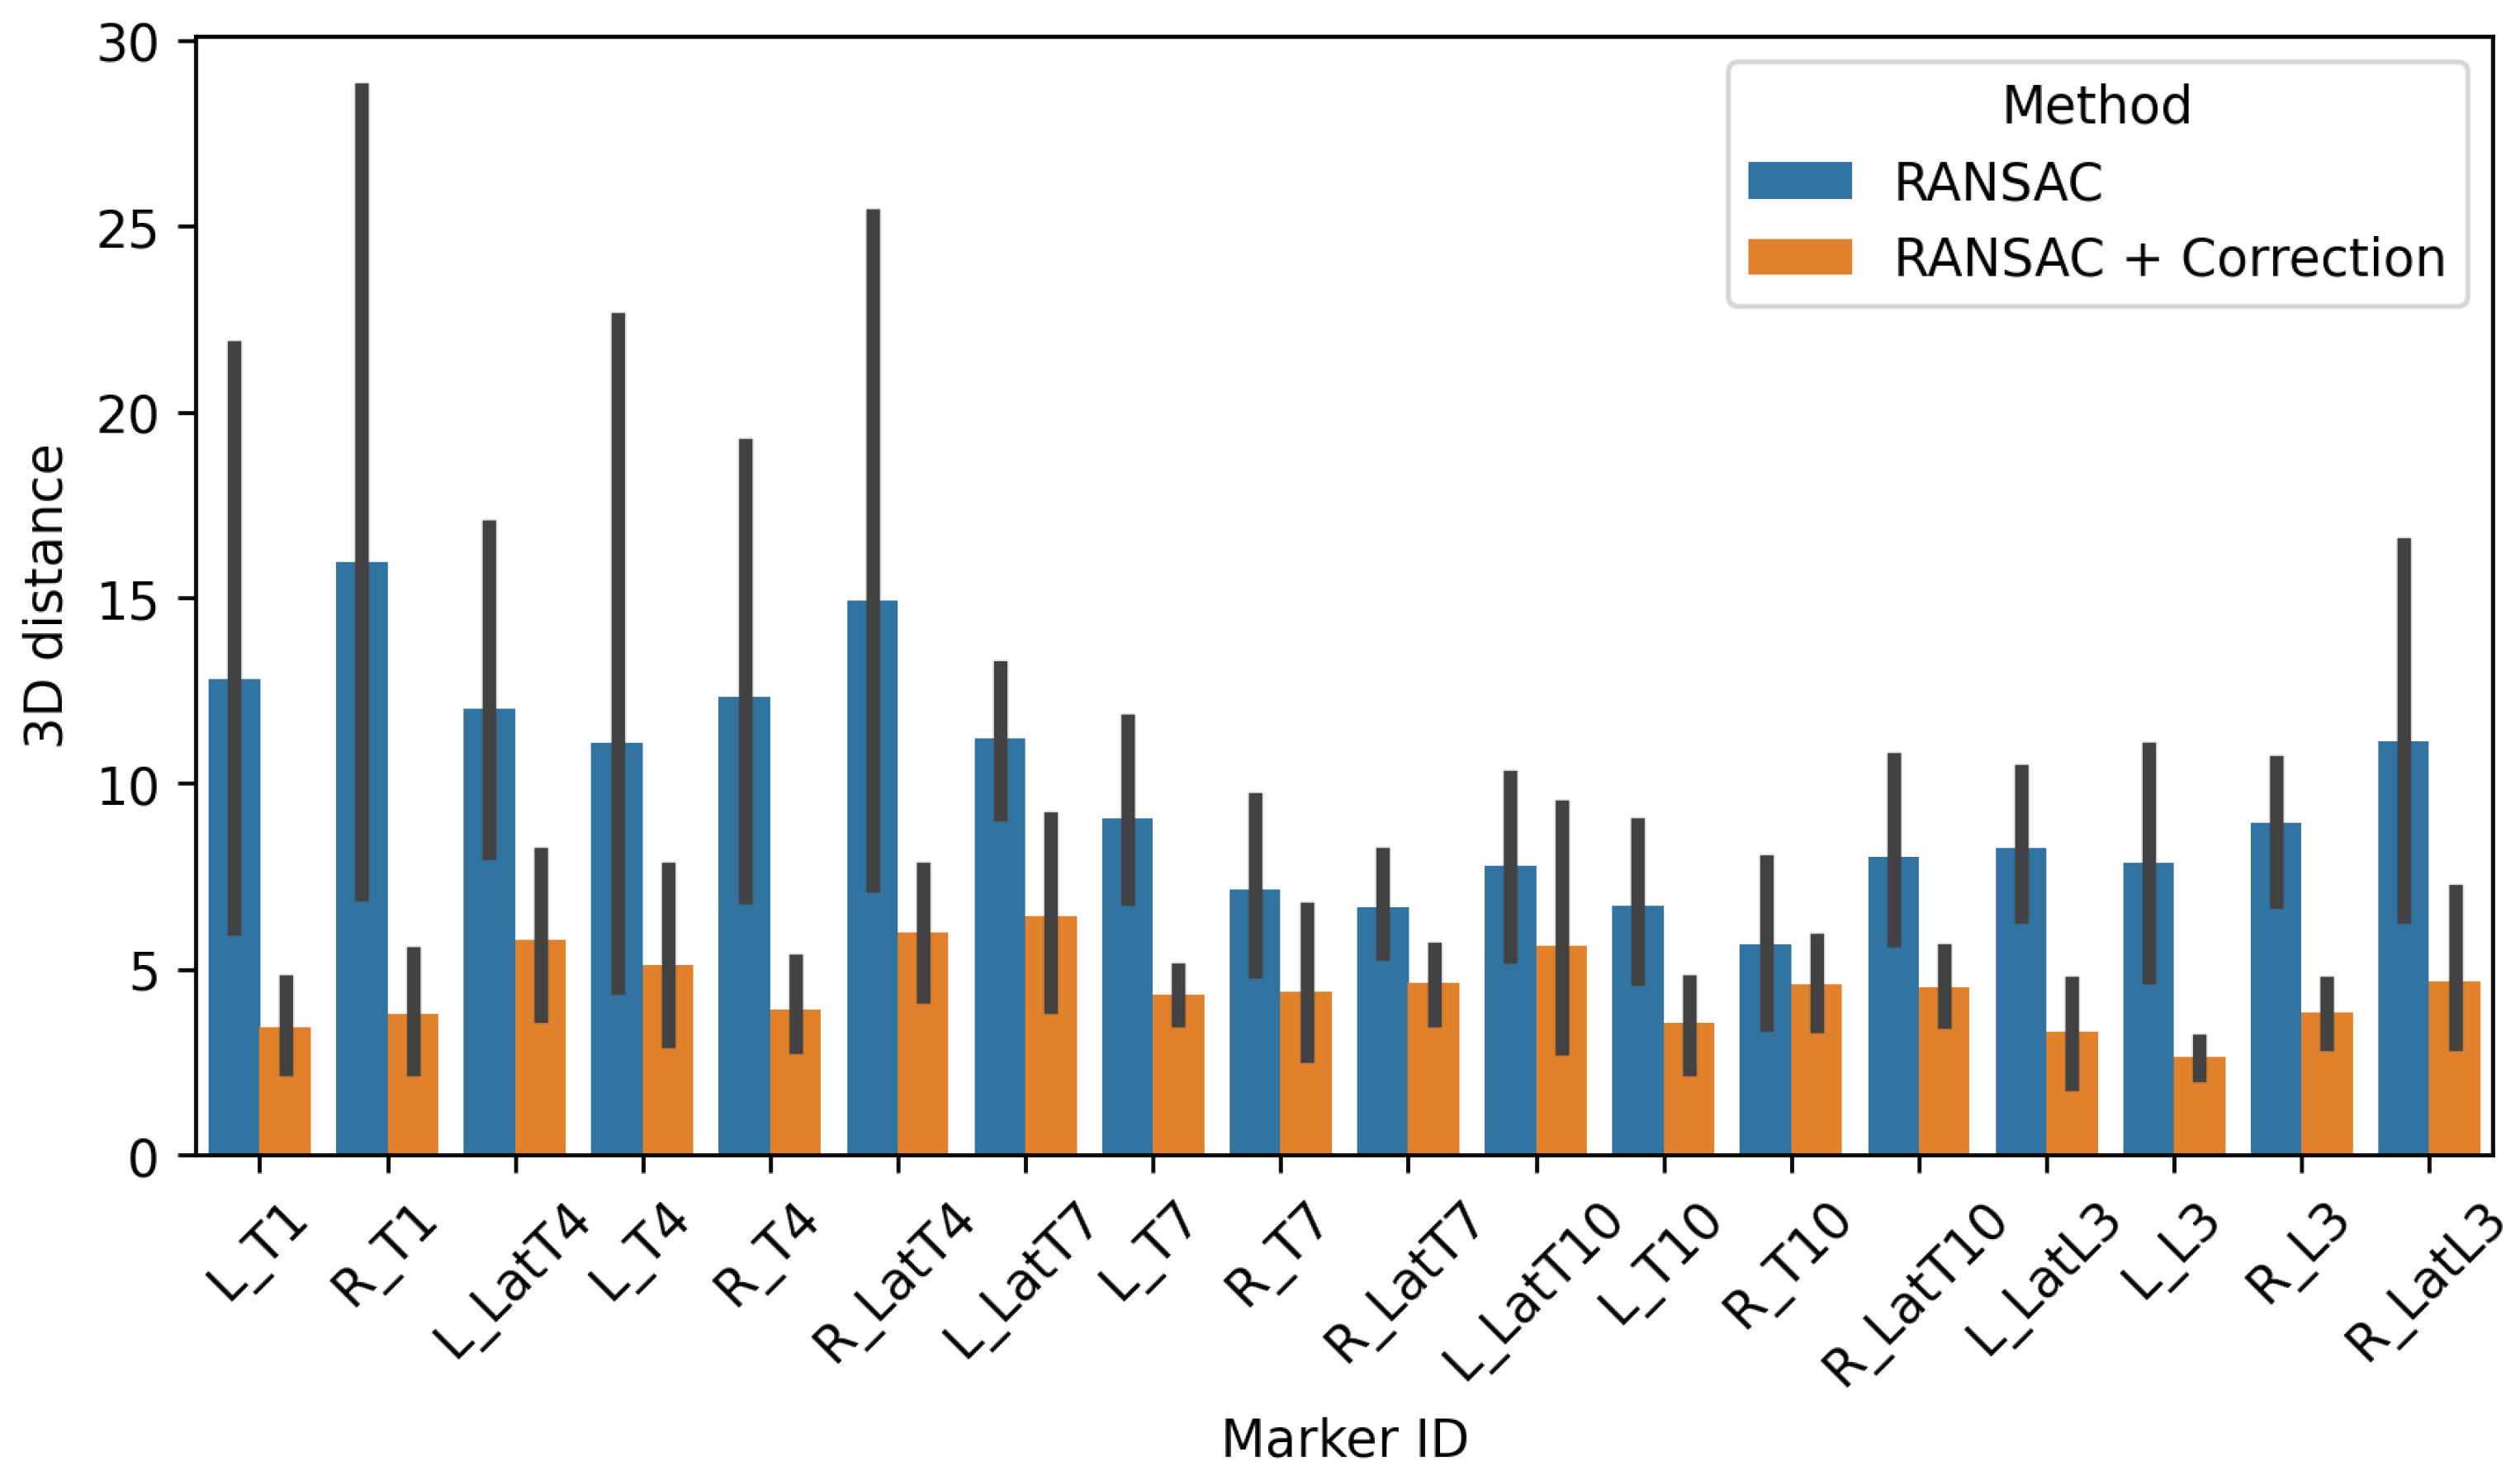

3.1. Accuracy of the Subject-Specific Model in Standing

3.1.1. External Accuracy

3.2. Accuracy of the Subject-Specific Model in Bending

3.2.1. External Accuracy